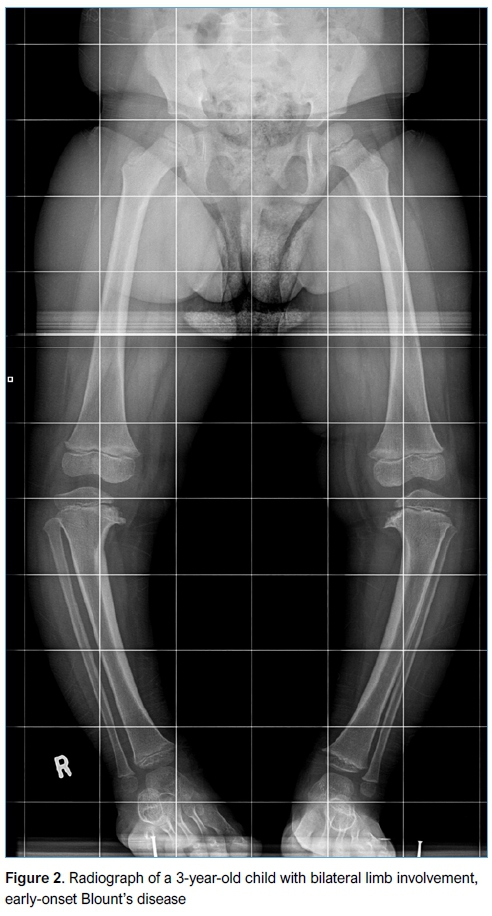

A total of 58 knees were studied radiologically (19 bilateral, 20 unilateral disease). Examples of the cases are illustrated in Figures 2 and 3. Using the Pearson correlations, no relationship was found between BMI and TFA (r=0.0342, p=0.8364). Using BMI to predict the Langenskiold classification for severity by the univariate logistic regression model, no association was found between BMI and Langenskiold classification (p=0.453). The mean TFA was 26.88° (range: 12-50) for early-onset disease and 27.4° (range: 4-54) for late-onset disease. Using cross-tabulation and Fisher's exact test to assess for an association between onset and Langenskiold classification, eight of nine patients with early-onset Blount's had low-grade (I-IV) Blount's disease (88.9%) whereas 56.7% of patients with late-onset Blount's disease had high-grade (V-VI) Blount's disease. This was statistically significant with p=0.023.